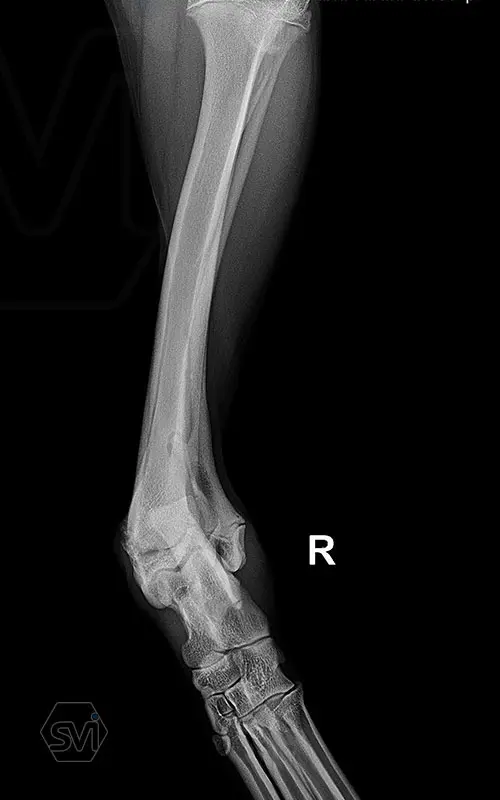

Multifunctional symmetrical long polyaxial locking plate - designed for the treatment of fractures close to joints

A special member of the polyaxial locking plate family is the multifunctional long plate, which is an extended version of the well-known symmetrical TPLO plate, with a 5-3 hole distribution. The plate also received a DCP hole to be able to create compression, and there is a mini-hole on the head end to facilitate the placement of the temporarily used K-nail. The burrs on the side facing the bone surface are intended to reduce the contact surface between the plate and the bone (limited contact).

The plate is a member of the large polyaxial locking family, suitable for 2.7-3.5-4.0 mm screws. We recommend it for fixaton of fractures close to joints, wedge osteotomies with axis correction (closing and opening), or for CWTO operations.